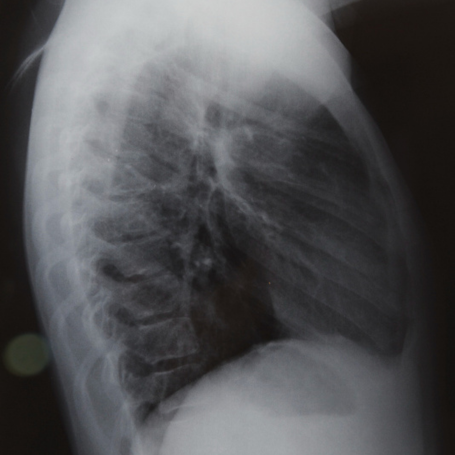

The Abdomen Lateral View (One Film) is a specialized X-ray imaging technique used to visualize the abdominal area from the side. It helps radiologists examine the position, shape, and structure of abdominal organs, detect blockages, identify abnormal gas patterns, and evaluate conditions such as intestinal obstruction, perforations, or foreign bodies.

Understanding the importance of this imaging test lies in its ability to reveal valuable information not always visible in a standard frontal X-ray view. The lateral view adds depth and detail to abdominal imaging, ensuring that overlapping structures are better visualized and evaluated.

Parameters evaluated in the Abdomen Lateral View include organ positioning, bowel gas distribution, fluid levels, and bone structures like the spine and ribs. This adds dimensional clarity that complements a standard anteroposterior (AP) abdomen view.